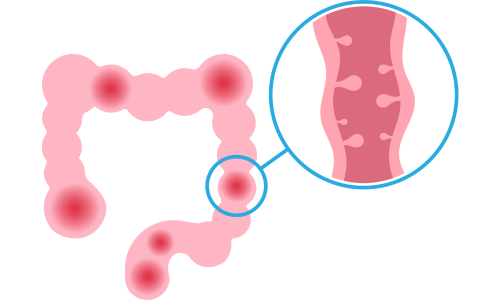

DIVERTICULAR ABDOMINAL PAIN Diverticular pain and diverticulitis refer to the presence of diverticula, small pouch-like projections that extend from the colon lining to its outer wall. This condition affects about...

DIVERTICULAR ABDOMINAL PAIN Diverticular pain and diverticulitis refer to the presence of diverticula, small pouch-like projections that extend from the colon lining to its outer wall. This condition affects about...